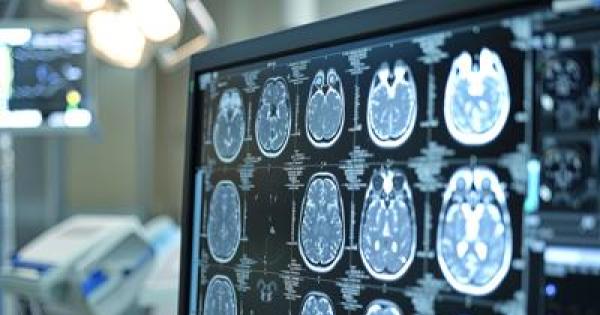

Roma, 27 ott. (Adnkronos Salute) - Una volta erano considerate delle neoplasie rare, ma oggi i gliomi sono sempre più diffusi. In Italia i casi annui ammontano a oltre 3mila e corrispondono al 40% di tutti i tumori cerebrali primitivi. Tra i gliomi, quelli di basso grado di frequenza più rara rappresentano una sfida clinica rilevante anche per la loro evoluzione e l'assenza di trattamenti mirati, oltre alla resistenza che dimostrano ai trattamenti convenzionali. Sono malattie orfane di cui si parla poco anche fra i clinici, tra le istituzioni e sui media. Perciò la Fondazione Aiom (Associazione italiana di oncologia medica) ha lanciato nei mesi scorsi 'I gliomi', una campagna nazionale online di formazione e informazione. Sono stati organizzati webinar rivolti agli oncologi medici e alle altre figure sanitarie coinvolte nel team multidisciplinare. Sono stati indirizzati a pazienti e caregiver ulteriori eventi online insieme a un'attività di sensibilizzazione sui principali social media. I risultati dell'iniziativa sono presentati oggi in una conferenza stampa virtuale promossa da Fondazione Aiom. Il progetto è stato realizzato con il contributo non condizionante del Gruppo Servier in Italia.

"Sono tumori cerebrali molto complessi e che spesso vengono diagnosticati in età giovanile - afferma Saverio Cinieri, presidente di Fondazione Aiom - Si sviluppano da cellule del cervello chiamate gliali e possono avere una prognosi variabile, ma potenzialmente a lungo termine. La gestione della patologia richiede una stretta collaborazione fra neurochirurgo, radioterapista e oncologo medico. Attraverso il bisturi è possibile rescindere la massa tumorale oppure eseguire una biopsia grazie a nuove e sofisticate tecnologie. La radioterapia permette di ridurre il rischio di recidiva o eliminare quella parte di cancro che non è stato possibile rimuovere chirurgicamente. Viene somministrata insieme alla chemioterapia e le sedute sono di solito diluite nel corso del tempo, per limitare l'impatto degli effetti collaterali. Infine, l'oncologo medico deve scegliere i farmaci da somministrare e deve selezionarli valutando le condizioni cliniche del singolo paziente".

"Anche per il trattamento dei gliomi, in particolare quelli di basso grado, si può ricorrere all'oncologia di precisione che potrà ridisegnare la pratica clinica nel prossimo futuro - illustra Enrico Franceschi, direttore dell'Oncologia del sistema nervoso all'Irccs Istituto delle scienze neurologiche di Bologna - E' molto importante verificare la presenza o meno delle mutazioni Idh1 e Idh2. Questi biomarcatori indicano specifiche patologie caratterizzate da una prognosi decisamente più favorevole e maggiore sensibilità dei gliomi alla radio e chemioterapia. Al momento della diagnosi è quindi essenziale l'esecuzione precoce di alcuni test molecolari per identificare al meglio i diversi sottotipi di gliomi. Tra le terapie di nuova generazione vi è anche vorasidenib, un farmaco orale inibitore Idh1 e Idh2 che ha dimostrato di essere un trattamento efficace nel posticipare la radio e chemioterapia nei gliomi di basso grado ed è una rilevante innovazione medico-scientifica".